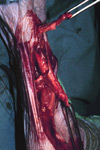

Tendon

Healing of tendon injuries is very complex. If we could rely on tendons healing in isolation to all other tissues surrounding them, then tendon healing would be greatly simplified.

Tendons do not possess sufficient cells to synthesise fibrous protein. Most of the cells in tendons (tenocytes) are probably inactive fibrocytes which do not have much capacity to `turn on' even after tendon injury. Indeed, tendon injuries that are isolated from surrounding tissues (eg. within tendon sheaths) are characterised by atrophy and resorption of the tendon ends. Therefore, regeneration of tendons has to depend on externally derived cells.

Fibroblasts from surrounding connective tissue migrate into the space between the tendon ends. Such cells excrete proteoglycans and collagen into the intercellular space, leading eventually to a dense fibrous scar. Adhesions extending from the tendon to surrounding tissues will occur. It is usually for the scar in association with the tendon ends will reform to some degree and subsequent collagen will realign longitudinally with the tendon. Such scar and collagen is never as strong as the original tendon and will be a potential site for further trauma.